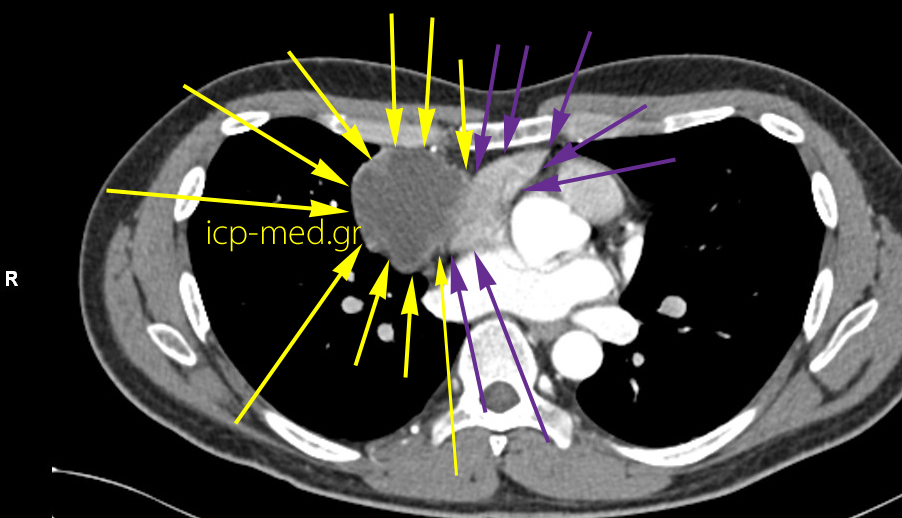

Σεμίνωμα Μεσοθωρακίου (α/παθές)

6.CT: Στενή επαφή Σεμινώματος με Δεξιό Κόλπο (καρδιακή κοιλότητα)